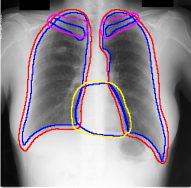

A few existing segmentation label noise approaches (Zhu et al., 2019; Zhang et al., 2020b; a) directly apply methods in classification label noise. However, these methods assume the label noise for each pixel is i.i.d. (independent and identically distributed). This assumption is not realistic in the segmentation context, where annotation is often done by brushes, and error is usually introduced near the boundary of objects. Regions further away from the boundary are less likely to be mislabeled (see Fig. 1(c) for an illustration). Therefore, in segmentation tasks, label noise of pixels has to be spatially correlated. An i.i.d. label noise will result in unrealistic annotations as in Fig. 1(b).

We propose a novel label noise model for segmentation annotations. Our model simulates the real annotation scenario, where an annotator uses a brush to delineate the boundary of an object. The noisy boundary can be considered a random yet continuous distortion of the true boundary. To capture this noise behavior, we propose a Markov process model. At each step of the process, two Bernoulli variables are used to control the expansion/shrinkage decision and the spatial-dependent expansion/shrinkage strength along the boundary. This model ensures the noisy label is a continuous distortion of the ground truth label along the boundary, as shown in Fig. 1(c). Our model also includes a random flipping noise, which allows random (yet sparse) mislabels to appear even at regions far away from the boundary.

For each of these three datasets, we use three noise settings, denoted by , and . and are two settings synthesized by our Markov process with (expansion) and (shrinkage), respectively. Figure 4 shows examples of our synthesized label noise. We also include the mix of random dilation and erosion noise used by previous work (Zhu et al., 2019; Zhang et al., 2020b; a). This is achieved by randomly dilate or erode a mask with a number of pixels. Note that our Markov label noise can theoretically include this type of noise by setting . Detailed parameters for these settings are provided in the Appendix.